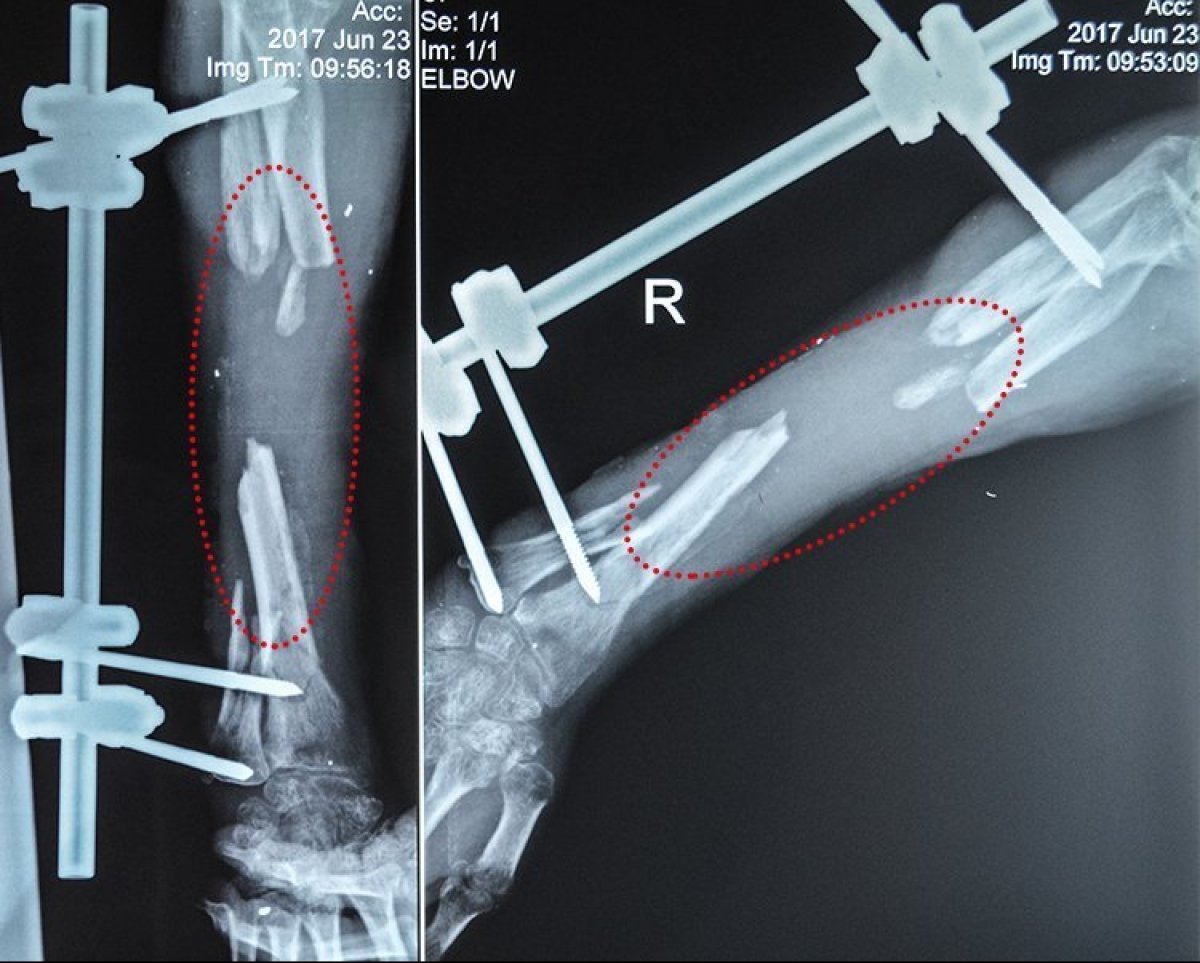

Унаслідок поранення Володимир має значні дефекти кісток передпліччя. Це практично неможливо якісно вилікувати за допомогою загальноприйнятих методик, додають у People`s Project.

"Крім того, вогнепальний остеомієліт прогресує та невпинно погіршує ситуацію: збільшує дефект кісткової тканини і з часом може призвести до втрати руки. Реконструктивно-відновлювальне лікування із застосуванням клітинних технологій допоможе подолати остеомієліт, компенсувати дефект та відновити цілісність кісток і, зрештою, максимально повернути функції руки", - наголошують волонетри.